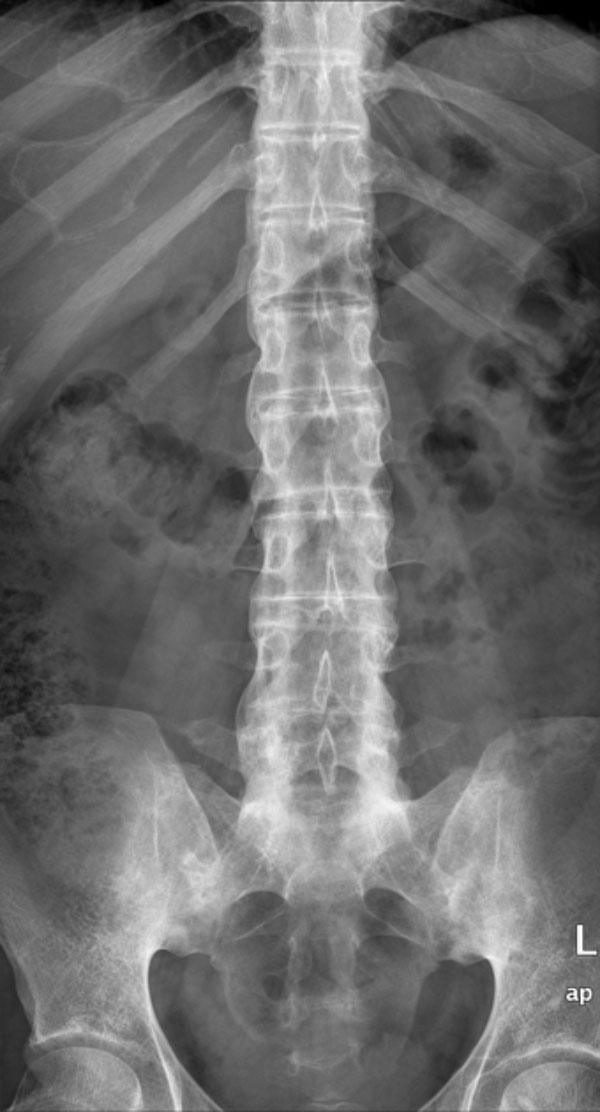

Chụp X-quang là phương pháp chẩn đoán hình ảnh viêm cột sống dính khớp được thực hiện đầu tiên giúp phát hiện các dấu hiệu viêm khớp cùng chậu, dính khớp cột sống và các thay đổi xương khác:

Hình ảnh X-quang viêm cột sống dính khớp có thể cho thấy các dấu hiệu như xói mòn xương, hình vuông hóa đốt sống, cầu xương (syndesmophytes) và dính khớp. Tuy nhiên, cần lưu ý rằng X-quang có độ nhạy hạn chế trong giai đoạn sớm của bệnh, khi các tổn thương viêm chưa gây ra thay đổi cấu trúc xương rõ ràng.

Sau đây là một số hình ảnh viêm cột sống dính khớp trên X-quang: